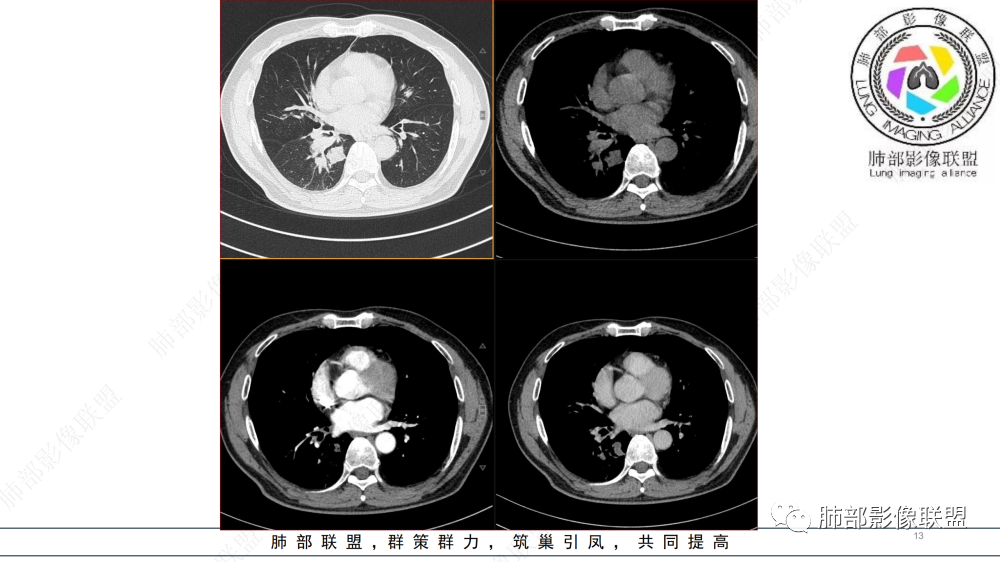

晨读 右肺中间段支气管至下叶支气管部分狭窄及堵塞,管壁偏侧增厚腔内外侵犯,软组织肿块形成,远侧肺内阻塞性炎症。考虑恶性病变,鳞癌,类癌可能

中年男性,咳嗽咳痰半年,有痰中带血,肿瘤标志物角蛋白稍高,右肺下叶支气管腔内肿块,支气管截断,有强化,考虑肺癌,鳞癌可能,鉴别类癌,粘液表皮癌等。

中年男性,痰中带血,病史半年,一直没有发热,感染指标不高,胸部CT右侧肺门不规则肿块影,边缘清楚,棘状突起,浅分叶,血管集支束,空泡征,不均匀强化,右肺斜裂结节状增厚,右侧中间支气管外压改变,右肺下叶背段支气管截断,无明显淋巴结肿大,恶性是没有问题,至于类型病灶大无坏死空洞,鳞癌靠后,无明显淋巴结肿大,小细胞靠后,所以腺癌首选。

晨读:男,57岁,咳嗽咳痰半年,右肺下叶支气管腔内肿块影,管壁增厚,管腔狭窄,增强扫描呈不均匀性强化,考虑恶性病变,鳞癌可能。

晨读病例,中年男性,咳嗽咳痰半年,有痰中带血,影像表现右肺下叶支气管腔内外占位,形态欠规则,有冰山征表现,支气管截断,有强化,考虑恶性病变,类癌或鳞癌可能,鉴别腺癌、粘液表皮癌等。

右肺下叶肺门区肿块,向中间段支气管突出,下叶支气管阻塞狭窄,腔内外侵犯,不均匀强化,内可见低密度,冠状位病变沿支气管走行生长,远侧肺内阻塞性炎症,考虑鳞癌,鉴别类癌